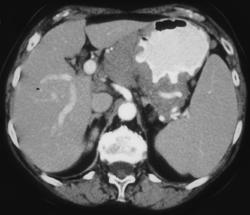

Gastric Adenocarcinoma With Extensive Nodes